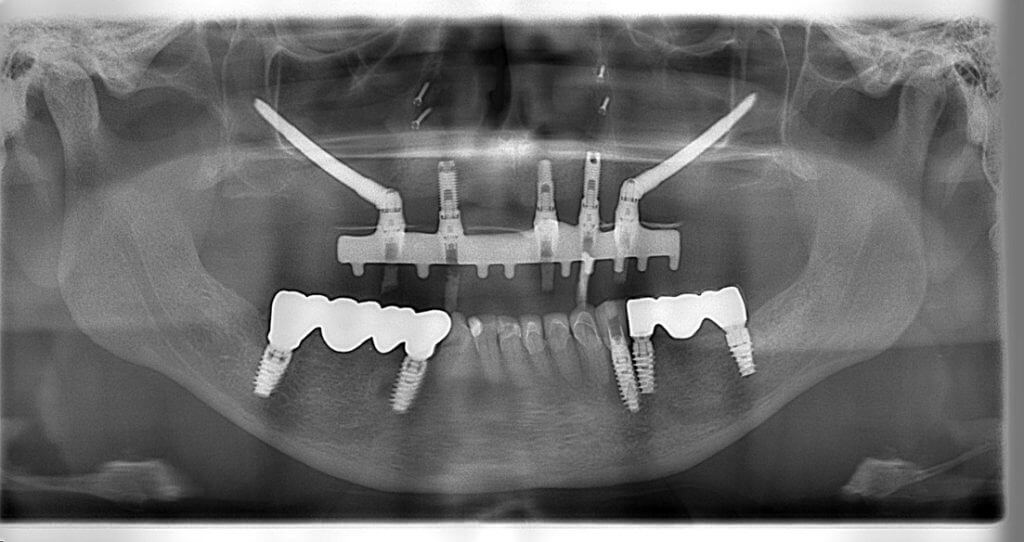

Another case involved a lady lacking sufficient jawbone for conventional dental implants (see previous image). She received conventional and zygomatic implants, allowing for a bridge anchored to the top jaw implants. She also had implants around the nose for better soft tissue support.

A woman with cancer of the mouth floor and front of the lower jaw underwent major surgery, including the placement of four dental implants. Three months later, these implants were exposed, ready for teeth attachment.